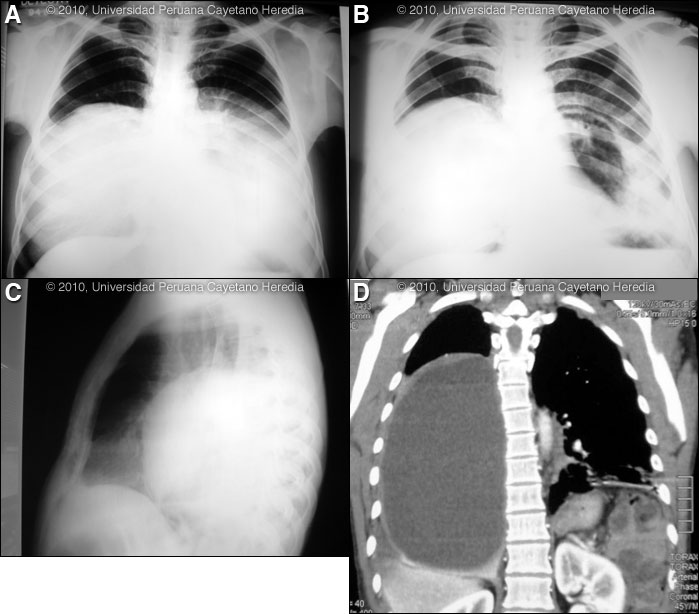

History: 43 year-old male first presented with a 2-year history of progressive dyspnea and dry cough. Two months later an acute deterioration occurred when he noticed that the cough became more severe with production of large amounts of liquid sour tasting salty sputum that did not appear purulent. The patient could not afford detailed medical evaluation. The dyspnea improved after this episode but has subsequently worsened. There have been some episodes of fever to which he received oral antibiotics of an unknown nature. Epidemiology: Born in the highlands of Perú where he worked raisingcattle. The patient has also worked in illegal gold-mining operations inthe Peruvian jungles for 25 years. No known TB contacts. No HIV riskfactors. Physical Examination: Afebrile, tachypnea (30 respirations per minute),pulse 90 per minute. Multiple inactive scars on skin from earlier episodesof leishmaniasis. Normal oral mucosa. Marked reduction in breathsounds in the right hemithorax with dullness; inspiratory rales in the base ofthe left lung. Rest of the exam is normal. Laboratory Results: Hemoglobin 14.2; WBC 7400 with normal differential,no eosinophils. Chest x-rays: Image A was taken at theinitial presentation; Images B and C were taken 2 months laterat the time of the acute deterioration. CT scan of the chest [ImageD] was taken 8 months later at the time of examination by the Gorgasparticipants. Abdominal ultrasound: normal.

Diagnosis: Echinococcus granulosus. Bilateral pulmonary hydatid cysts. Acute rupture of left cyst into a main bronchus.

Discussion: A Western blot taken before the acute rupture was strongly positive for E. granulosus. The expectoration of large amounts of salty fluid is highly characteristic of this catastrophic event. The CT scan showed a giant cystic lesion that occupies ¾ of the right hemithorax with displacement of the mediastinum. The residual cavity in the posterior left lung has surrounding parenchymal inflammatory infiltrates. Human hydatid disease secondary to Echinococcus granulosus is caused by the larval form of this dog tapeworm. Humans ingest the tapeworm eggs in environments contaminated by canine feces and become accidental intermediate hosts. This patient had ongoing exposure to dogs while working in the cattle raising industry. Sheep are the normal intermediate hosts. Larval cysts expand slowly over years or decades, becoming symptomatic as they impinge on other structures by virtue of their size. Spontaneous cyst rupture as occurred here happens in the minority of cases but is not rare. The cysts contain hundreds of viable protoscoleces capable of becoming adult tapeworms upon ingestion by a definitive host such as the dog. The internal germinal membrane lining the cyst produces new protoscoleces on an ongoing basis. Each protoscolex is capable of becoming a new daughter cyst should the original cyst rupture or be ruptured. However it is unusual to see secondary pulmonary cysts from bronchial seeding after a rupture of a cyst into a bronchus, as in this case. This is probably due to adhesion of protoscoleces to mucus secretions in the airways and to ciliary movement that will eliminate the protoscoleces subsequent to the cough reflex. An example of seeding of the pleural cavity after an intraparenchymal rupture is seen in a previous case of the week [see Gorgas Case 2005-10]. Cystic hydatid disease due to E. granulosis is common in sheep and cattle raising areas worldwide. Most primary infections involve a single cyst. 65% of solitary cysts are found in liver, 25% in lung and the rest in a wide variety of other organs including kidney, spleen, heart, bone and brain. In patients with a pulmonary cyst, approximately 18% will also have a hepatic cyst. Bilateral lung hydatid cysts are present in 6% of adults but in up to 30% of children in whom pulmonary involvement is generally more frequent [Pediatr Radiol. 1978 Sep 26;7(3):164-71]. In our experience in Perú 3.8% of pulmonary cysts are bilateral. Pulmonary hydatid disease affects the right lung in 60% of cases. Serology is usually positive with hepatic cysts but sensitivity drops below 50% with solitary pulmonary cysts even when the cyst is large. With the large burden of disease in this patient’s lung a positive serology would be expected. Praziquantel is the most potent scolicidal drug and is the drug of choice for all adult tapeworms. However, praziquantel cannot penetrate the hydatid cyst wall, so it is only useful as an acute therapy when a cyst ruptures (spontaneously or due to surgical mishap) and scoleces are lying free before encysting again. Albendazole is the therapy of choice for intact cysts that are not operable, such as when there are multiple or disseminated cysts. A trial of albendazole may also be considered for solitary cysts that are less than about 10 cm. Response is generally slow and only complete in a minority of cases. Surgical resection is the therapy of choice for large intact cysts. Experimental protocols using combined praziquantel and albendazole are underway in several places, but a patient with extensive disease would still not be a candidate for medical therapy only. The patient is going to be transferred to Lima for further surgical management of his disease. The surgical approach to bilateral hydatid disease of the lungs has not been the subject of any systematic trials or retrospective reviews of outcomes and the approach is surgeon dependent. Bilateral disease may be managed by one- or two-stage surgery. Some prefer two-stage thoracotomy, operating on the side with the larger, ruptured, or infected cyst first as a more cautious approach. However, when feasible, many consider a median sternotomy single-stage combined resection to be the approach of choice, and it is less traumatic and painful for the patient. Visualization of a typical pulmonary hydatid cyst at the time of surgery was shown in one of our previous cases [see Gorgas Case 2008-02]. Technical aspects of surgery are reviewed [Respiration. 2000;67(5):539-42; Eur Respir J. 2003 Jun;21(6):1069-77]. In the case of pulmonary cysts many surgeons feel that cyst softening that may occur with perioperative albendazole makes the operative procedure more complicated and increases the risk of rupture at the time of resection. No data from trials is available.